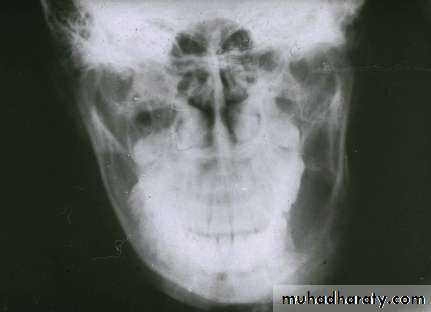

• Maxillary lesion may produces pressure effect and nasal obstruction

• Radiography:• Uni or Multilocular radiolucent areas

• Soap bubbles